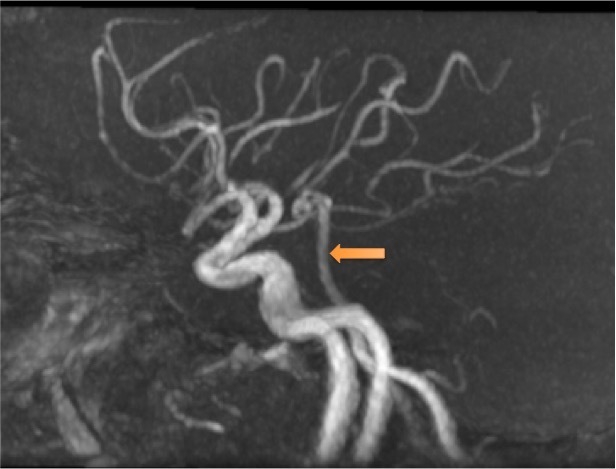

Voici l’angiographie par résonance magnétique (ARM) du polygone de Willis réalisée chez ce patient.

Question 4 : Concernant les structures légendées, quelles sont la/les proposition(s) exacte(s) ?

Artère cérébrale moyenne également appelée artère sylvienne.

Artère cérébrale antérieure gauche, naissant (hors variante anatomique) de la terminaison de la carotide interne homolatérale. Les deux artères cérébrales antérieures communiquent par une artère communicante antérieure dont la naissance est située à l’union de leurs deux premiers segments.

Artère cérébrale postérieure droite. Celles naissent du tronc basilaire communiquent avec le système carotidien via les artères communicantes postérieures (une de chaque côté).

Tronc basilaire, formé par l’union des deux artères vertébrales en intracrânien

Artère carotide interne gauche. La division de l’artère carotide commune en artère carotide interne et externe est située en extracrânien à hauteur de C4.

À noter que le polygone de Willis peut présenter de nombreuses variantes anatomiques qui peuvent avoir une répercussion en cas de pathologie artérielle (présence ou absence de suppléance via les anastomoses entre les systèmes carotidiens d’une part, carotidien et vertébro-basilaire d’autre part).